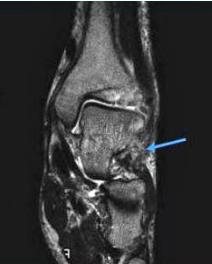

(八)跗骨窦综合征MRI检查

MRI检查适用于创伤后不明原因的持续性疼痛患者,有助于早期发现跗骨窦部位病理改变。正常跗骨窦在冠状位和矢状位MRlT1加权图像上显示高信号强度的脂肪和低信号强度的韧带组织,若跗骨窦脂肪为其他组织代替,T1、T2加权图像则均为广泛低信号强度改变,且可显示颈韧带和骨间韧带撕裂 。

跗骨窦综合征MRI表现

跗骨窦韧带撕裂,窦内结构模糊跗骨窦韧带纤维化(在T1WI和T2WI图像上呈低信号)

滑膜炎、液体和韧带扭伤(T1WI低信号;T2WI高信号)

在距下关节后面前、后微隐窝处的液性信号(T1WI低信号;T2WI高信号)

常见到踝外侧韧带撕裂,外踝肿胀